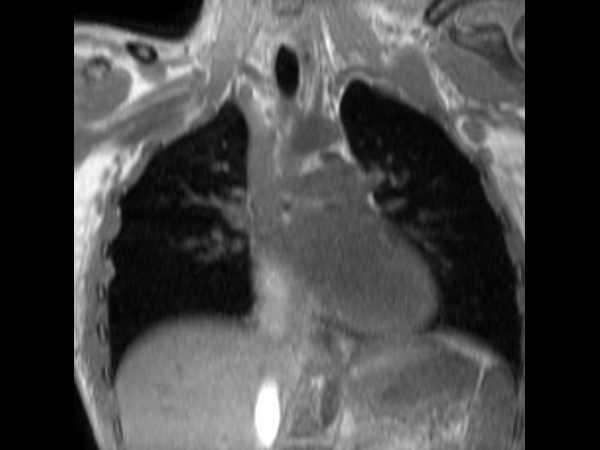

T2w TSE - MultiVane XD